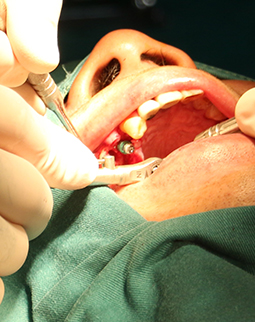

“准备做手术了,大爷您别紧张,我们有四个人呢,您看这个是给你种牙的博士,我是给您负责巡航的护士,还有俩助理,您放心。”68岁的我真躺在手术椅上,护士在给我做术前的精神疏导,这次我终于下定决心种牙,希望能让缺牙的牙重新长出来了。

躺在牙椅上,佩戴好心电监护,看着给我种牙的医生团队有条不紊,我感到安心,但还是有点小紧张。躺在手术椅上我的在想,68岁了,不必再为孩子而活,接下来我的晚年生活可能更多姿多彩,我规划好了,接下来我准备出去旅游,准备学个摄影,准备约上战友成立个钓鱼队,准备吃遍天下美食,准备过个轰轰烈烈的夕阳年。

面对我参差不齐的骨量,整个团队都围绕着我想方案,最终确定了给我骨粉骨膜搭配植骨的方式重新夯实我的骨量,老爷子我很感恩。